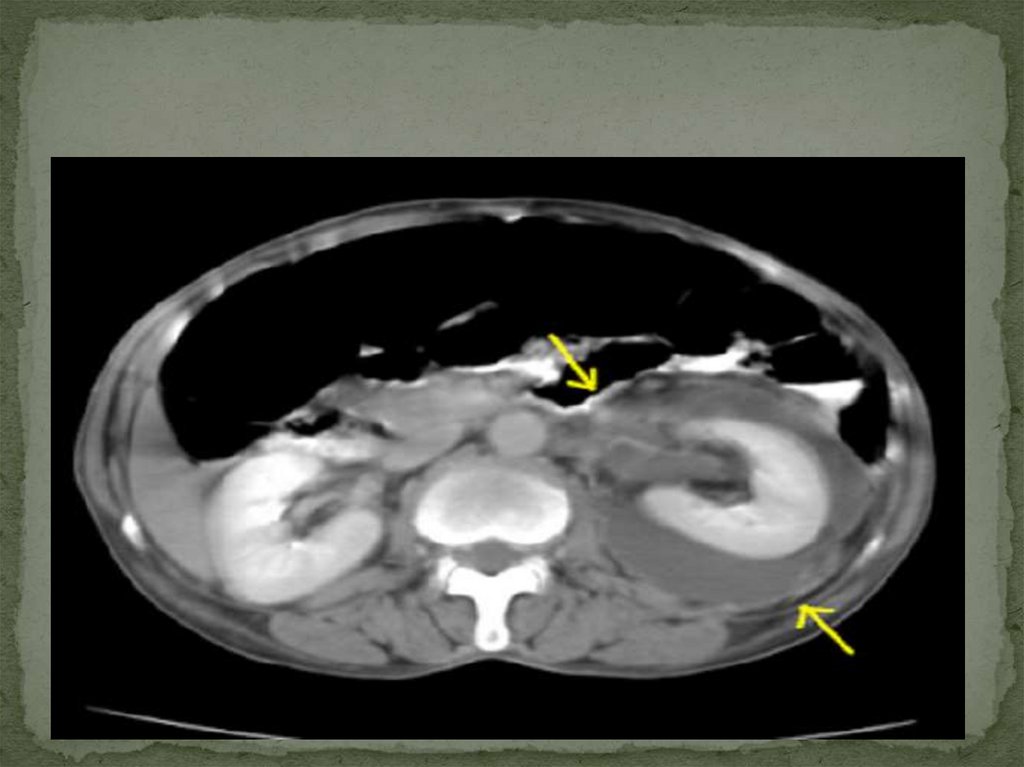

Бел аймағының шолу рентгенограммасында

омыртқаның бел бөлігінде зақымдану жағына

қарай қисаю, анық бүгілу немесе осы жағынан бел

бұлшықетінің контуры жиегінің болмауы жиі

кездеседі. Несепағардың жоғарғы бөлімі жиі сау

жаққа жылжиды. Жедел іріңді паранефритте

құнды ақпарат ультрадыбыстық зерттеу және

компьютерлік томография береді